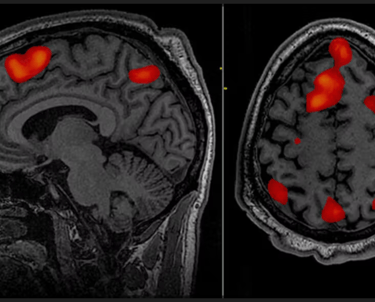

Published in the journal Nature by psychiatrists at Weill Cornell University. Functional magnetic resonance imaging (fMRI) scanners were used to compare the brain activities of clinically depressed and healthy people.